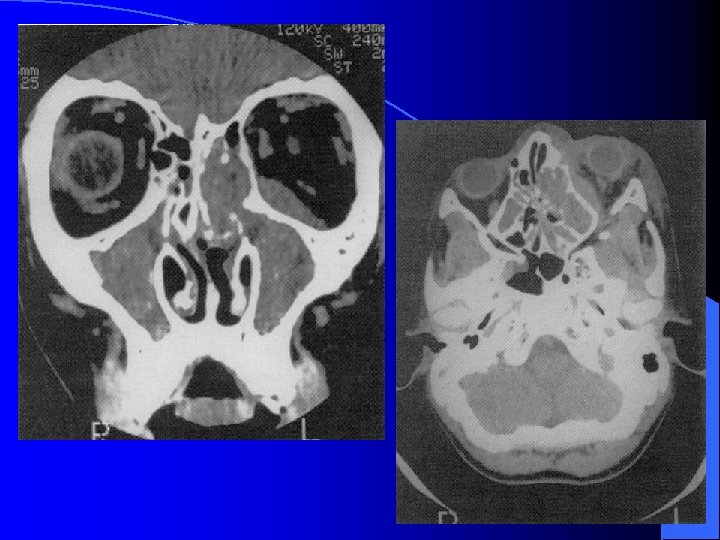

Ethmoïdite aiguë suppurée droite

Forme extériorisée = TDM

MALADIES INFECTIEUSES RHINO SINUSIENNES ETHMOIDITE AIGUË IMAGERIE • Radiographie standard • Echo doppler couleur (opérateur dépendant) • TDM sans et avec injection siège, stade collecté, analyse orbitaire fine